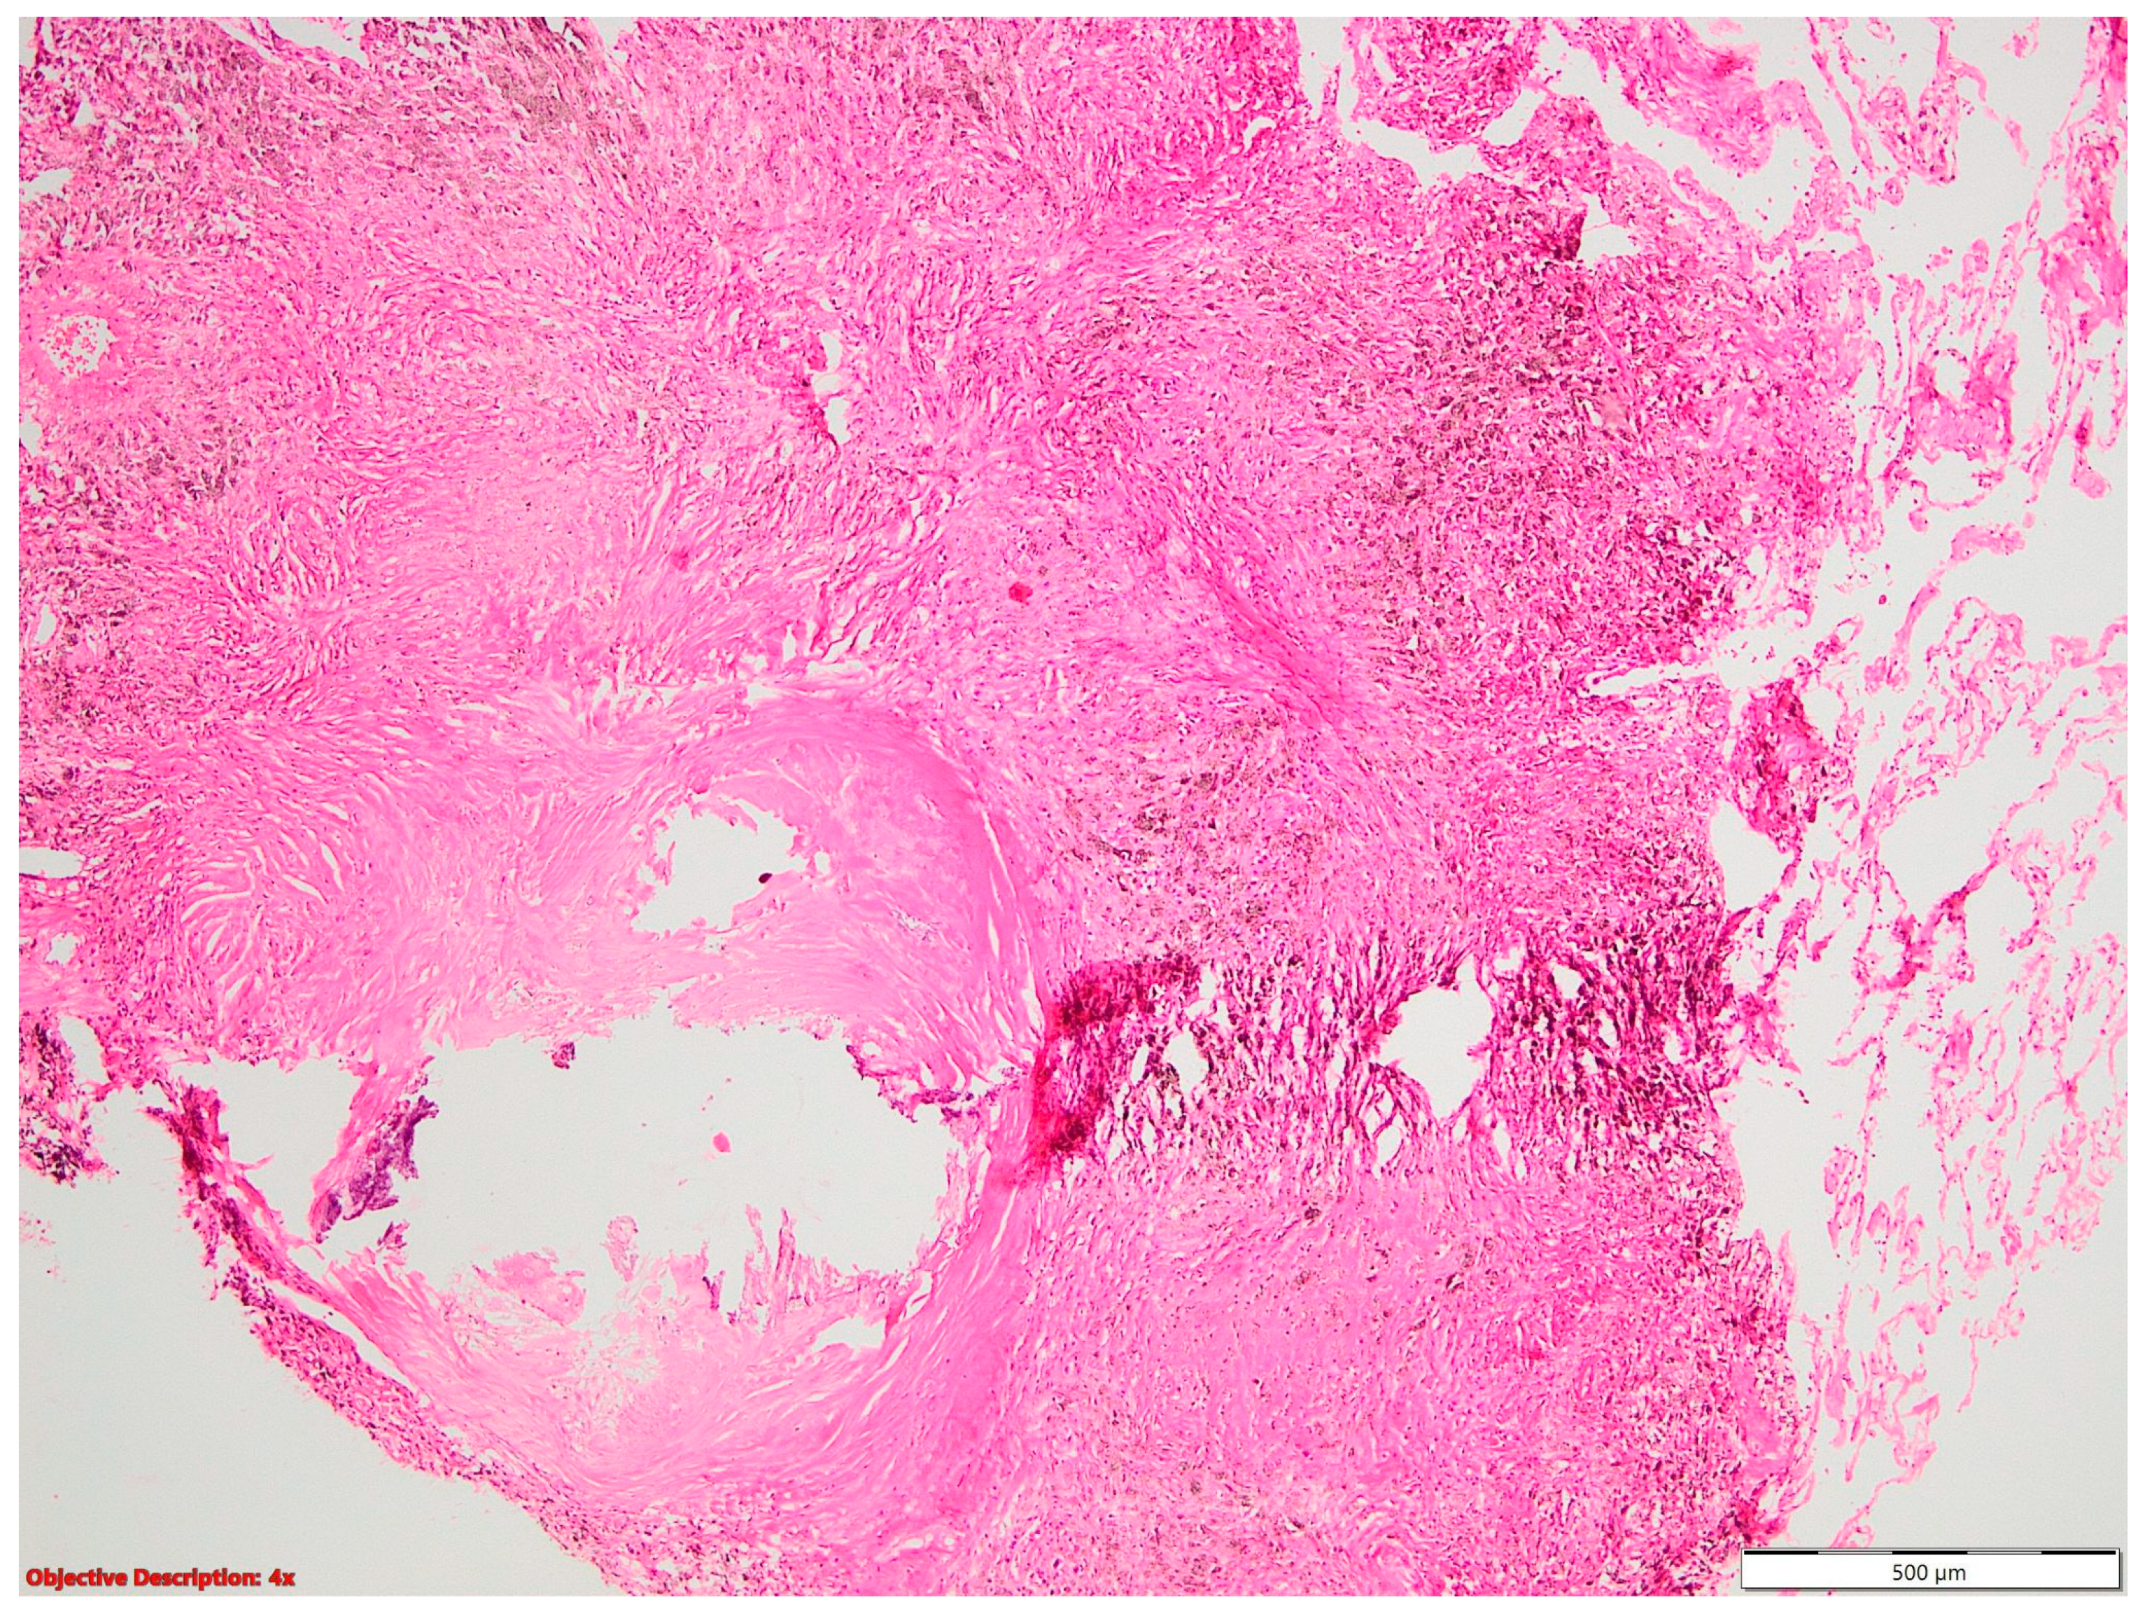

Two of the specimens with fibronodular lesions were associated with multiple NSCLC tumors of different histopathological subtypes: one case presented with adenocarcinoma (one tumor—Figure 6) and a squamous cell tumor (one tumor—Figure 7) and another case presented with adenocarcinoma (one tumor) and large-cell neuroendocrine tumors (two tumors—Figure 8).

Figure 6.

Lung adenocarcinoma: (a) gross examination (white tumor with polycyclic contour and anthracotic deposits); and (b) microscopic examination (tumoral glands that replace the normal lung parenchyma); HE, 40×.

Figure 7.

Lung squamous cell carcinoma (large polygonal cells with infiltrative pattern of growth; keratinization is evident →); HE, 40×.

Figure 8.

Large-cell neuroendocrine cell carcinoma with abundant tumoral necrosis; HE, 40×.